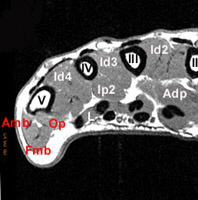

Le Court Fléchisseur du petit doigt (Fmb) fait partie du plan superficiel des Muscles de l'Eminence Hypothénar.

Fusiforme et grêle, oblique en bas et en dedans, en avant de l'opposant

Se fusionne distalement avec l'abducteur du V

Tubercule médial de la base de P1 et sur le sésamoïde médial de la MCP